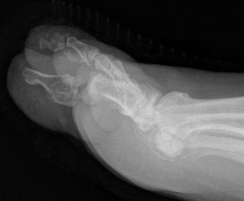

Interphalangeal joint dislocation

Pathology

Hyperdorsiflexion

P1 head dislocates plantar

Blocks to closed reduction

Sesamoid interposition

Open Reduction

Dorsal Approach

- protect dorsal superficial nerve

- divide capsule medial to EHL

Reduce +/- K wire